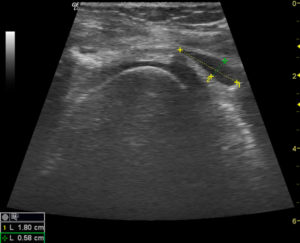

Экскреторная урография при нефроптозе: диагностические изображения